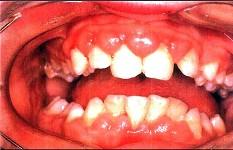

问题 患者,男性,19岁,主诉:前牙牙龈红肿肥大1年余。临床检查:上唇短,上前牙唇侧牙龈边缘及龈乳头增生肥大,覆盖牙冠的1/3,质地较韧。最可能的诊断是()

选项 A.青春期龈炎 B.急性坏死性溃疡性龈炎 C.慢性龈缘炎 D.增生性龈炎 E.牙龈纤维瘤病

答案 D